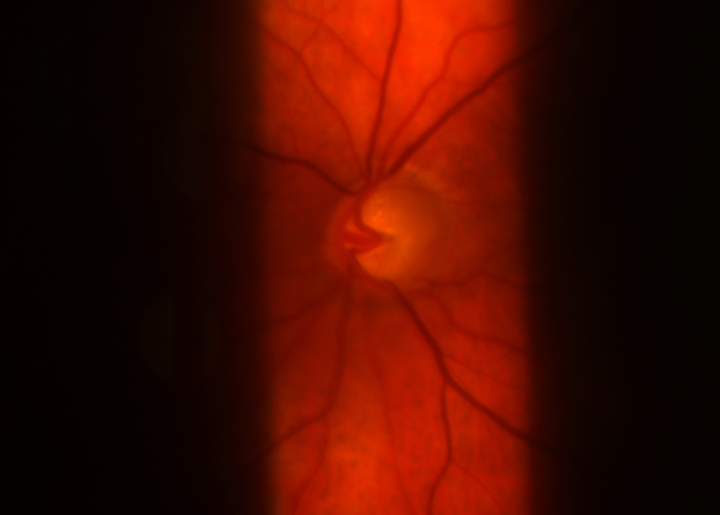

The ClearPod diverts fog away from your lens surface giving you ample time to conduct detailed exams without having to interrupt care.

No more asking patients to remove their masks, dealing with messy tape, or using solutions that erode your lens coatings!

LIFT THE FOG

The unique shield has carefully designed wing and flange features to efficiently direct warm currents of air away from your optical path.